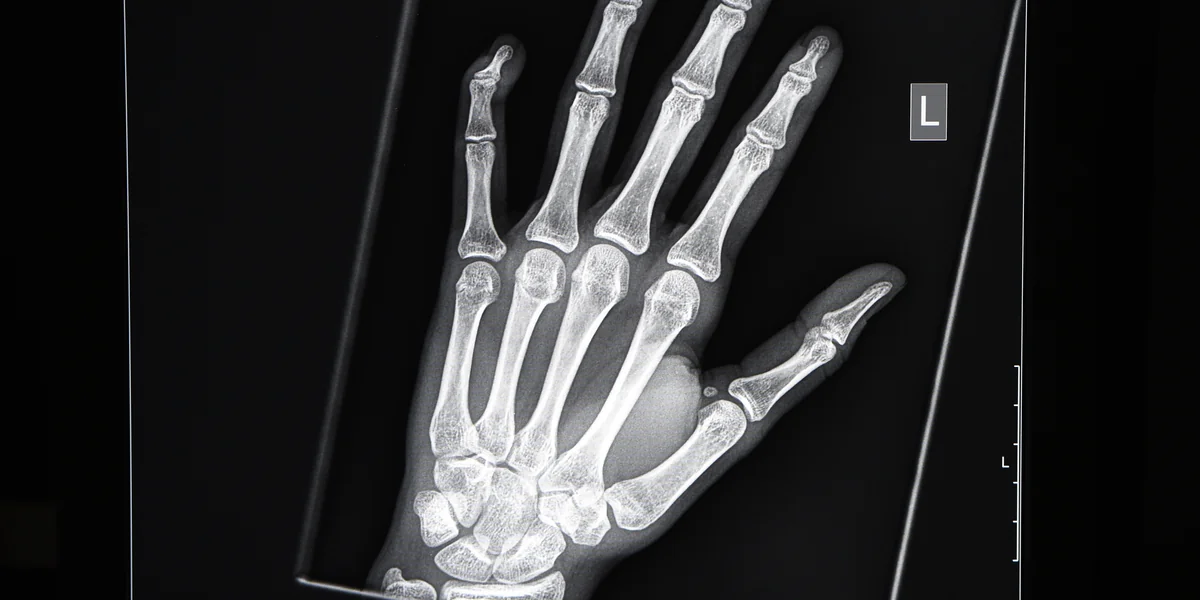

Röntgenbild von der linken Hand eines jungen Menschen im Alter von 16 bis 19 Jahren Foto: dpa

Um das Knochenalter zu bestimmen, wird die linke Hand geröntgt. Die Radiologen schauen sich die Handwurzelknochen an und untersuchen, in welchem Entwicklungsstadium sie sich befinden. Bei kleinen Kindern sind diese Knochen nur Kerne, die dann mit der Zeit wachsen und größer werden. Dabei schließen sich die sogenannten Wachstumsfugen. Bis zum 19. Lebensjahr sei dieser Prozess in der Regel abgeschlossen, erklärt Yen. „Danach kann man keine weiteren Aussagen mehr machen.“ Anders bei den Schlüsselbeinen: Wenn Kinder zu Erwachsenen werden, schließt sich die Wachstumsfuge im Bereich des Brustbeins – in den meisten Fällen geschieht das spätestens bis zum 26. Lebensjahr. Für diese Untersuchung wird ein Computertomograf eingesetzt.